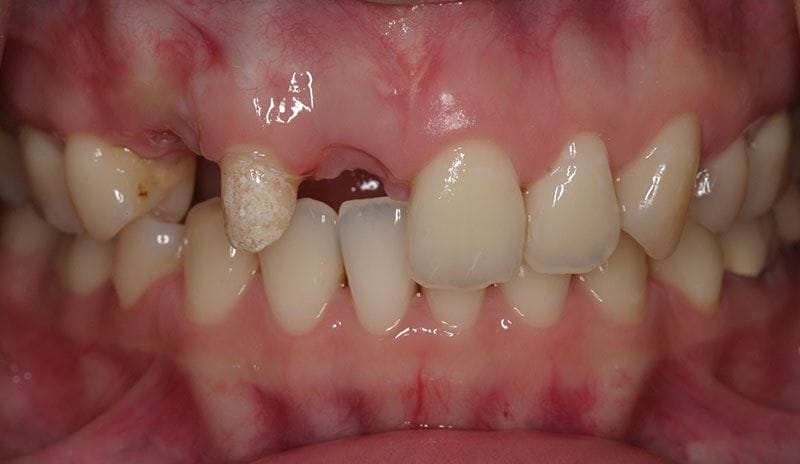

陳小姐是一位美貌與才氣兼具的事業女強人,在一次晚宴中,已經做了十多年的門牙假牙脫落,陳小姐緊急求助黃醫師,立刻進行"立即式植牙" ,將已經蛀壞的牙根拔除,植入人工牙根,再做上美觀的假牙,讓陳小姐無後顧之憂的面對明日的工作。

治療前